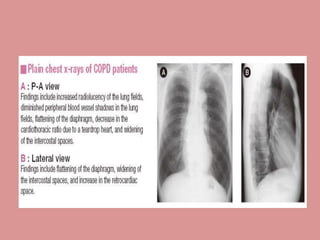

• X-Ray - An x-ray of the chest may show an over-

expanded lung (hyperinflation) and can be useful to

help exclude other lung diseases.